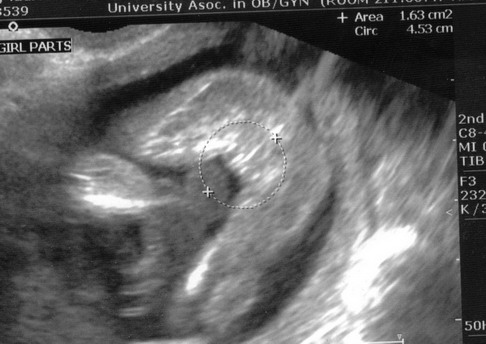

I had the three lines and they've checked 3 times (15 weeks, 20 weeks, and 30 weeks). Here is my 15 week "coochie" shot with her 3 lines (if yo ucan see the little arrow pointing at them)

I can never make out what I am looking at in those photos. What are those two things to the left of it, feet?

yep..pretty sure those are her feet!

Posted by btrflygrl

My sono at 17 weeks looked like this. DH won't let me "find out" what we're having, but based on this, I'm pretty certain it is a girl. I'll really feel awful if it is a boy, and "he" wasn't fully formed yet, but I was calling him a girl.